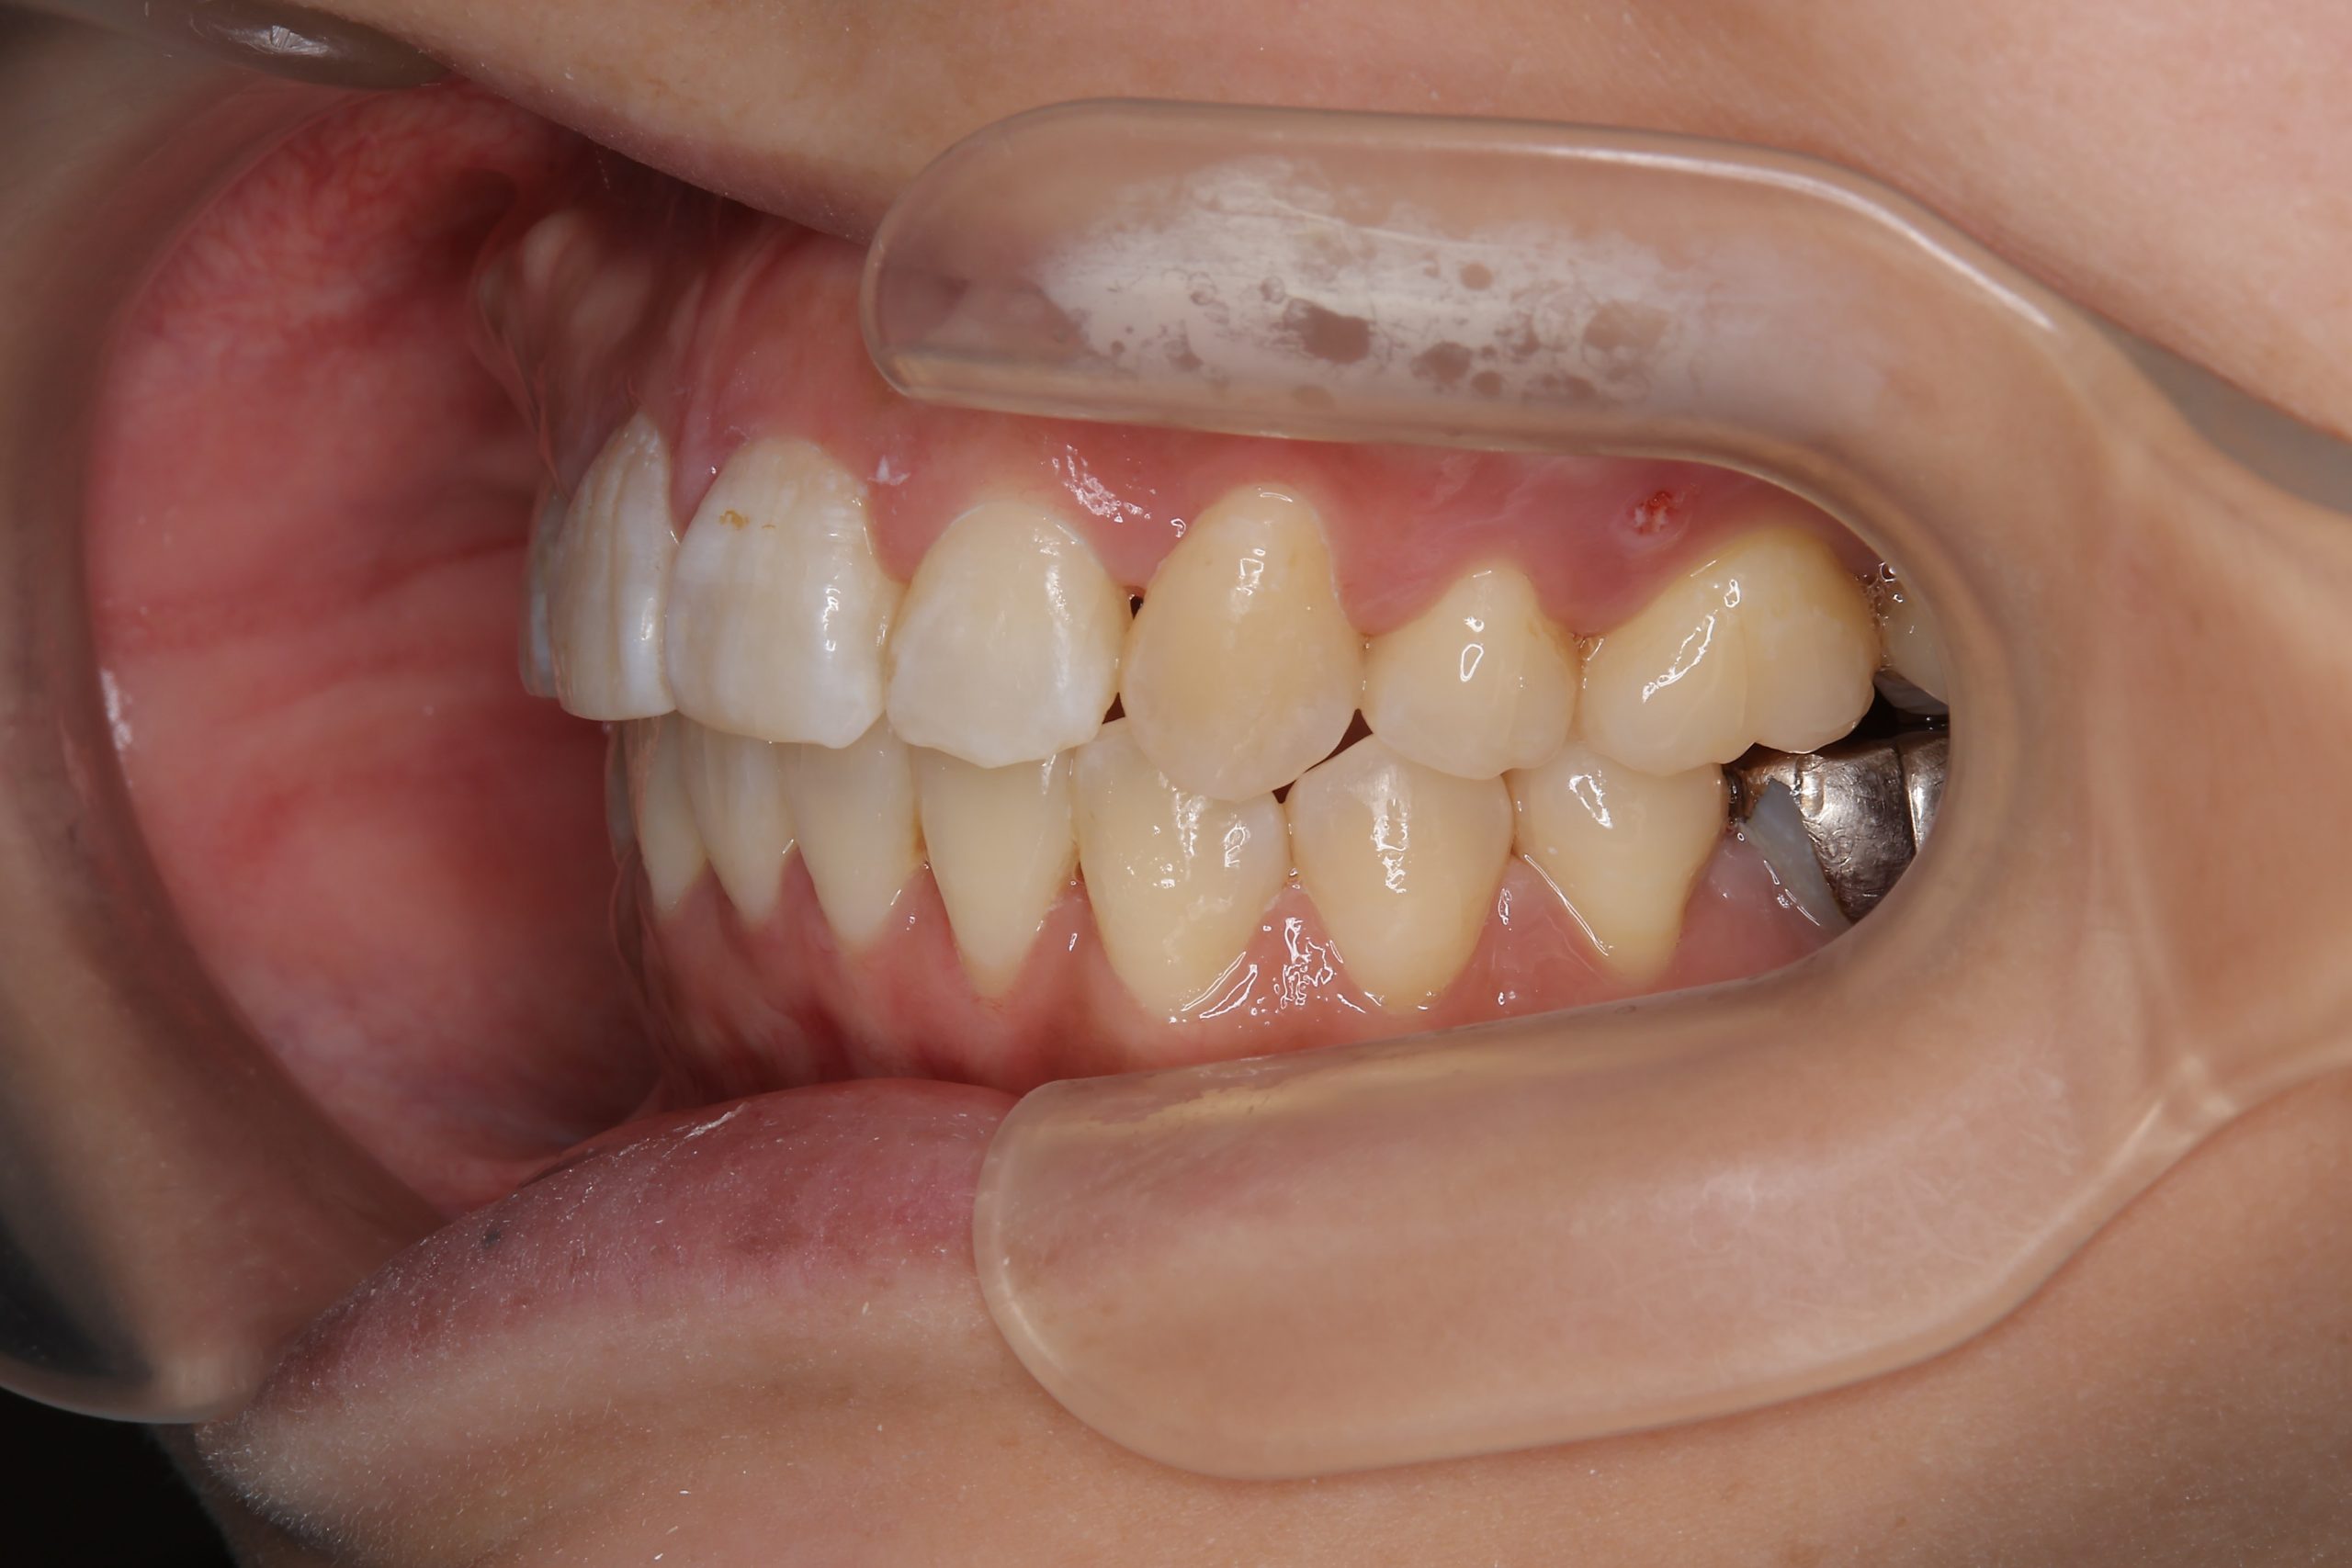

ビフォー

ワイヤー矯正治療|症例_814

主訴 八重歯

施術内容 MSEと下顎リンガルアーチを用いて上下顎骨を拡大した。

その後上顎3・4番を抜歯しマルチブラケット装置とミニインプラントを用いて

歯牙を配列した。良好な咬合を獲得した。